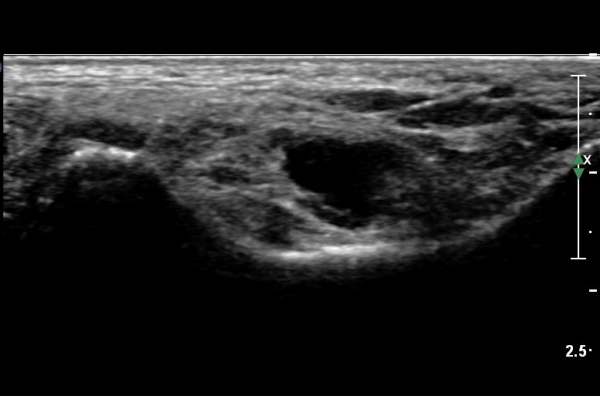

ŽÃËÀÚ¸¦ Á¶±Ý ¸»´ÜÀ¸·Î À̵¿ÇÏ´Ï Èİæ°ñ½Å°æÀÌ ³»ÃøÁ·Àú½Å°æ°ú ¿ÜÃøÁ·Àú½Å°æÀ¸·Î ºÐÁöÇÑ´Ù(»çÁø 2).